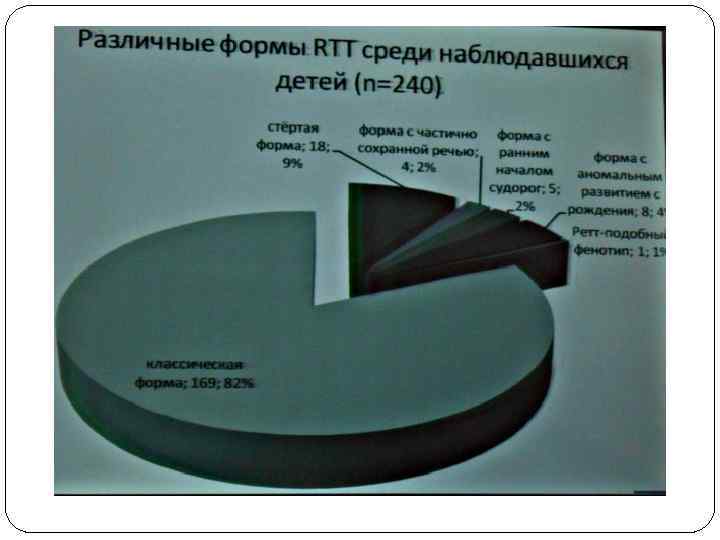

У ряда больных клинические признаки не соответствуют полностью классическому течению синдрома Ретта. Эти случаи классифицируют либо как неполные, либо как атипичные формы заболевания. При неполной форме у больного присутствуют многие, но не все из необходимых симптомов. Этим характеризуются легкие варианты болезни. Атипичные формы — это случаи синдрома Ретта, которые соответствуют всем необходимым критериям диагностики, но имеют отклонения от типичного течения. В частности, при атипичной форме синдрома с ранним началом судорог эпиприпадки являются дебютом заболевания. При атипичном варианте синдрома с частично сохраненной речью больные имеют некоторые речевые навыки, течение заболевания у них более мягкое, чем при классической форме, а уровень общения значительно выше. Известны также атипичные варианты синдрома с аномальным развитием ребенка с рождения, поздним началом фазы регресса, сюда же относят случаи синдрома Ретта у мальчиков.